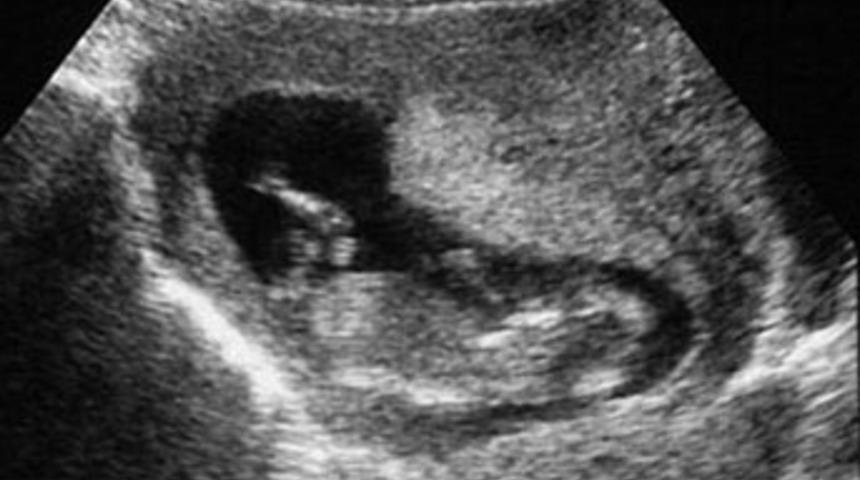

ABD'nin Ohio eyaletinde dokuz haftalık bir ceninin ultrason görüntüleri ve kalp atışı kayıtları, kürtaj yasağı oturumunda 'ifade' olarak dinlenecek.

Eyalet meclisi komitesinin konuyla ilgili oturumunda, ilk kez söz konusu kayıtlar bir ekrana yansıtılarak delil olarak sunulacak. Hamile bir kadınnı ultrason görüntüleri bu ekrana yansıtılacak.

Görüntüde ceninin kalp atışları renkli olarak da gösterilecek.